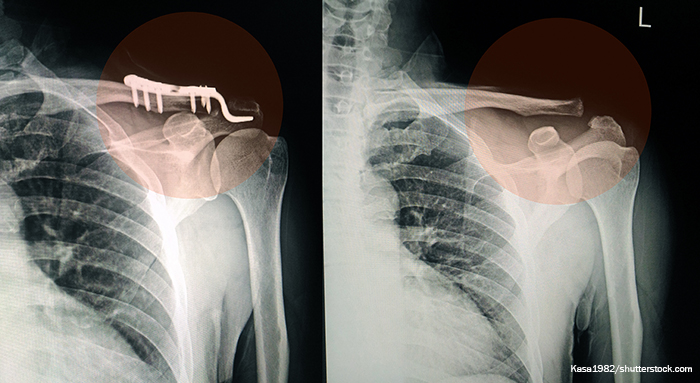

The team studied 309,330 of the 18 most common bone fractures, as well as medication use, including antibiotics, anticoagulants, diabetes medications, osteoporosis medications, cardiac medications, diuretics, immunosuppressants, steroids, anticonvulsants, and non-opioid analgesics in addition to opioid analgesics. They found that opioid medications as a class significantly increased the risk of fracture nonunion following both acute and chronic administration.

The researchers report that Schedule II opioids, as a group, create a greater nonunion risk than non-opioid analgesics. Certain of these medications produce a significant risk, including acetaminophen/oxycodone, hydromorphone, acetaminophen/hydrocodone, oxycodone and meperidine. Of the Schedule III-V opioids, tramadol and naloxone/pentazocine were also associated with increased risk. Acetaminophen/codeine and buprenorphine were not associated with increased risk of nonunion. Prescription NSAID use also increased the risk of nonunion among chronic users.